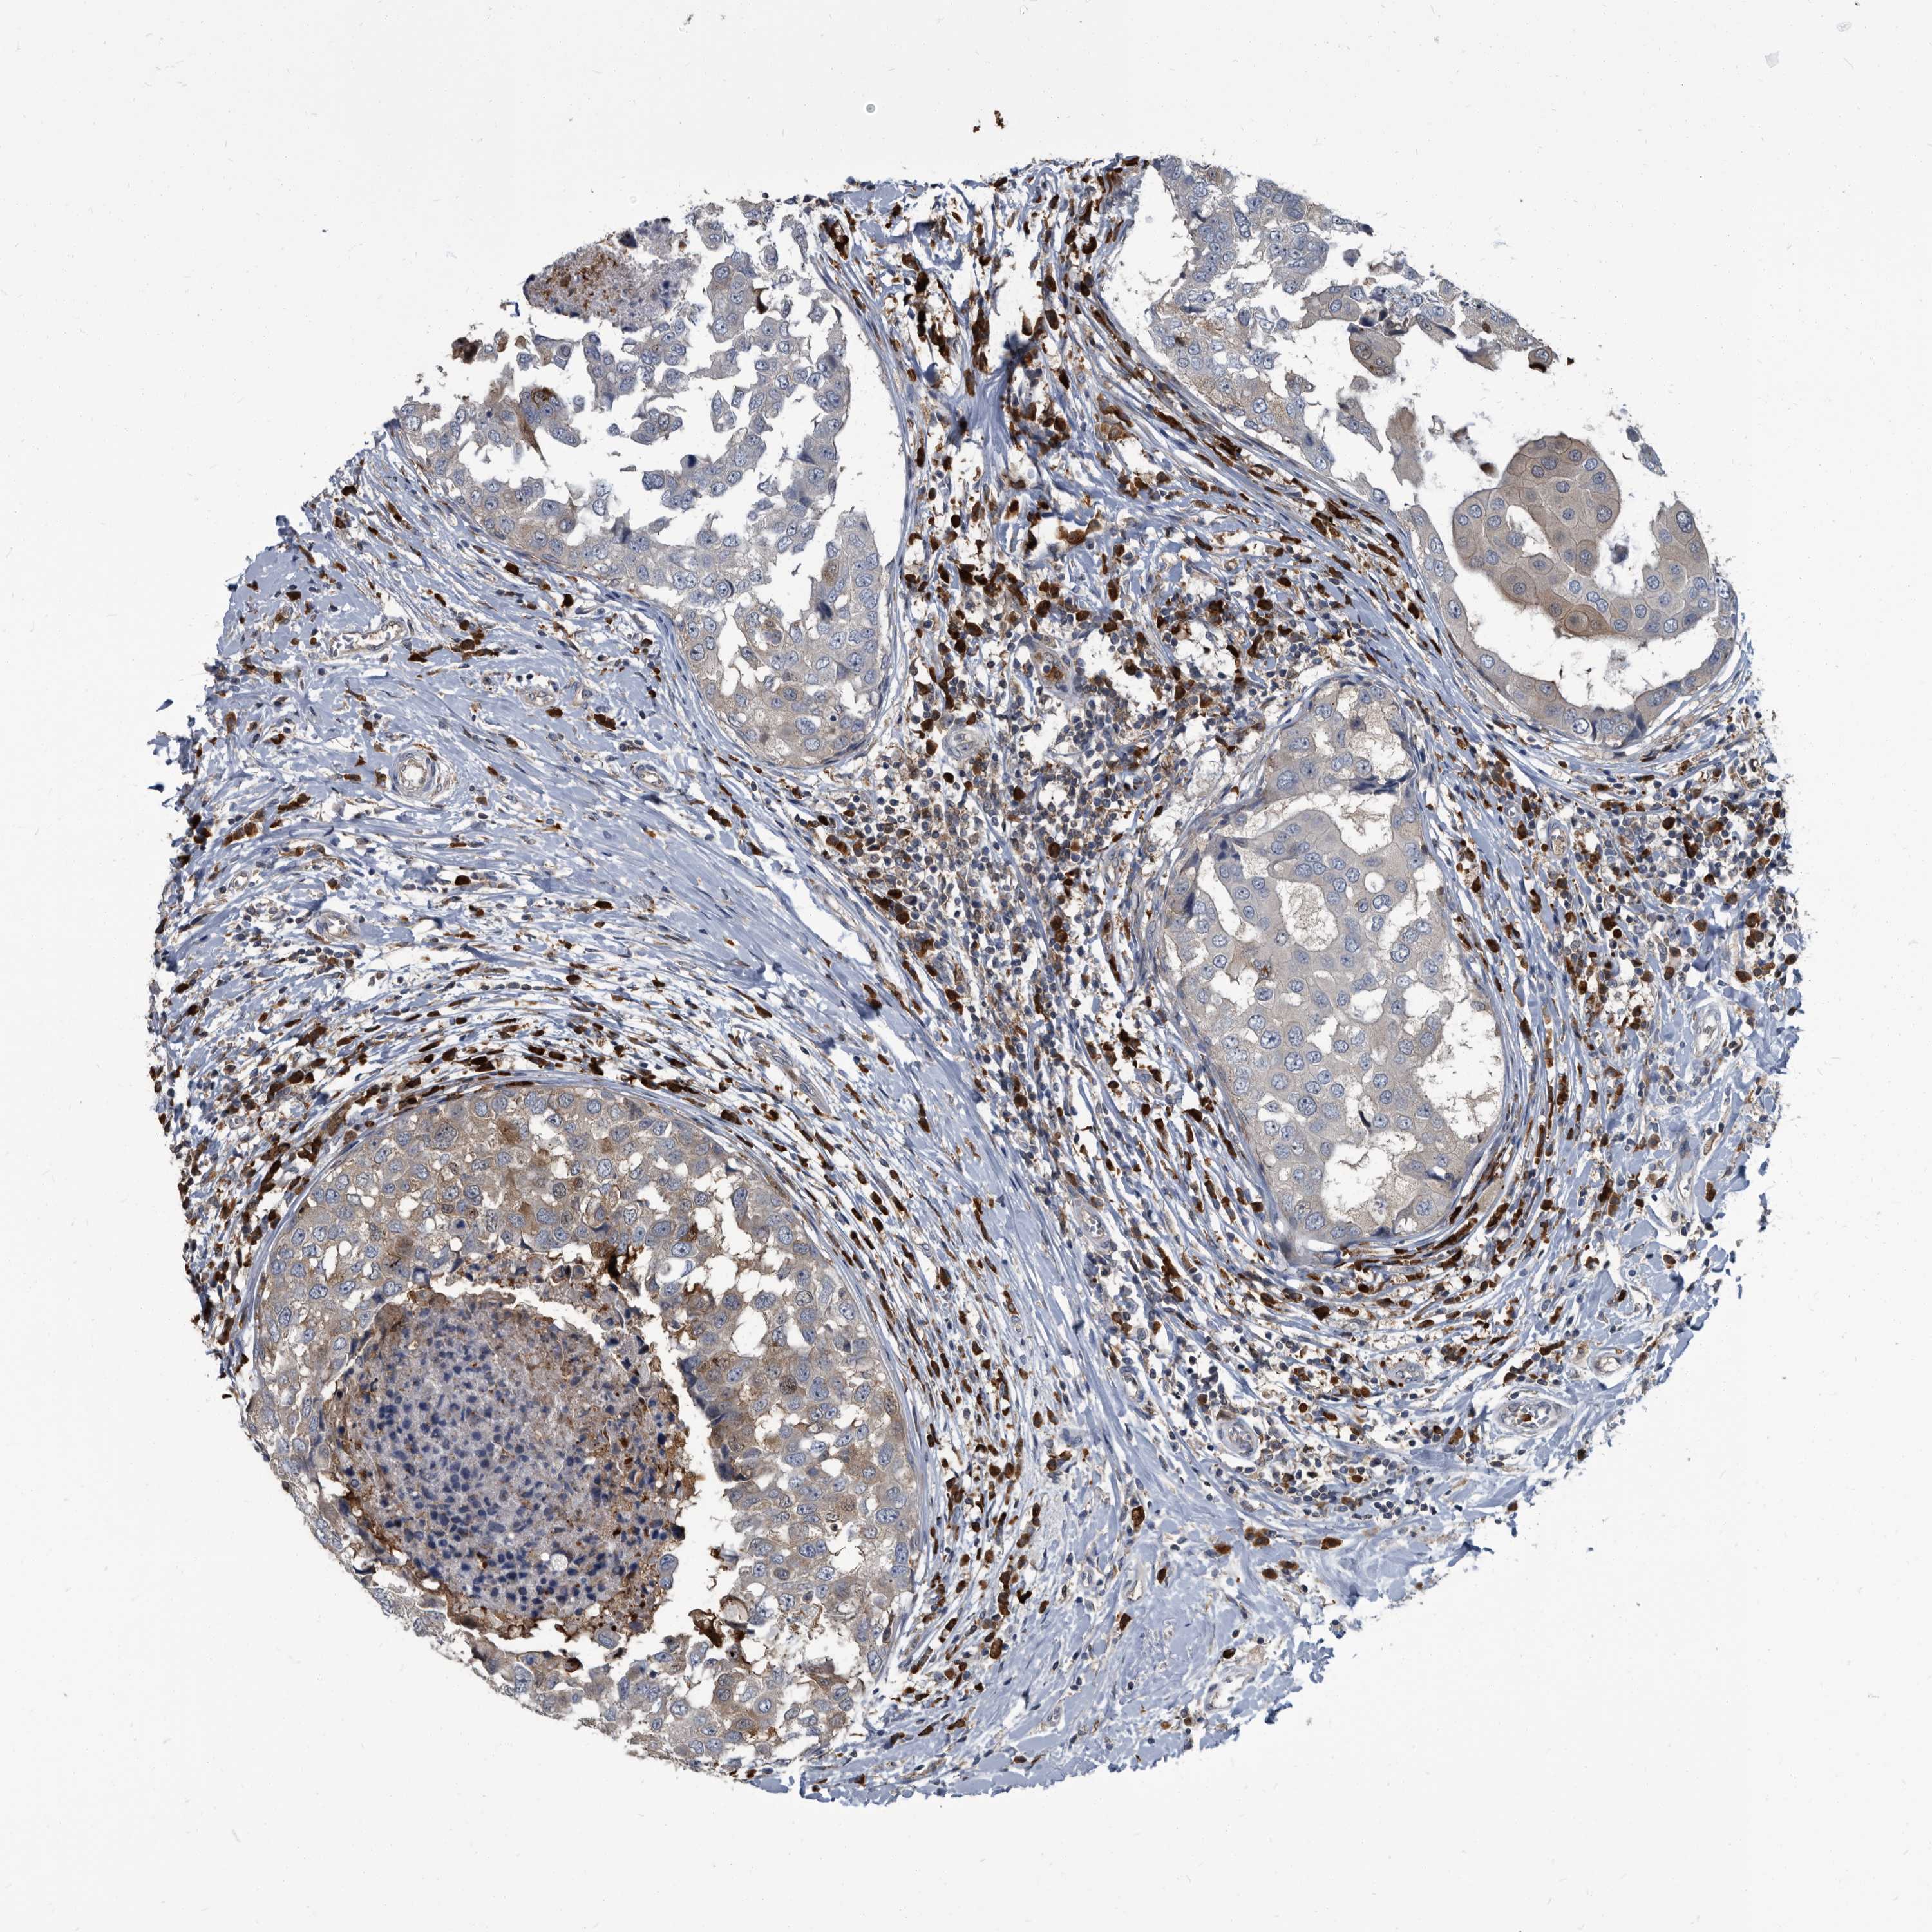

CANCER BREAST CANCER Show tissue menu

BRCA TCGA BRCA VALIDATION PROTEIN EXPRESSION